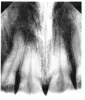

С февраля появилась боль в 11-ом зубе, только когда я на него надавливаю пальцем (не снизу, а прямо от губы). Кушать и стучать по нему не больно. Сделал снимок, нерв вроде нормальный. Сам зуб чистый без кариеса. Удалять нерв не советуют, так как нет показаний. Назначили вчера озонотерапию (уколы озона в десну через шприц). Нигде не нашел, что озон вкалывают в десну.

Необходим очный осмотр, в пришеечной области 11-го зуба, есть небольшое пятно. Возможно, это не кариозное поражение, которое провоцирует чувствительность и боль в зубе.